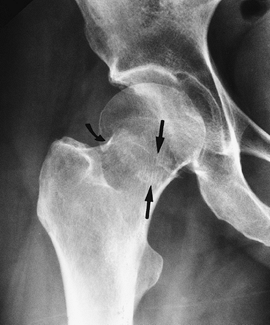

FIGURE 4-14 Impacted femoral neck fracture (arrows) with cortical disruption and trabecular compression laterally (curved arrow). The hip was pinned.

|

FIGURE 4-15 (A) Displaced femoral neck fracture (arrow). (B) Treated with bipolar endoprosthesis.

FIGURE 4-16 Coronal fast spin-echo T2-weighted image demonstrates edema with a central linear low-intensity line (arrow) caused by femoral neck stress fracture.